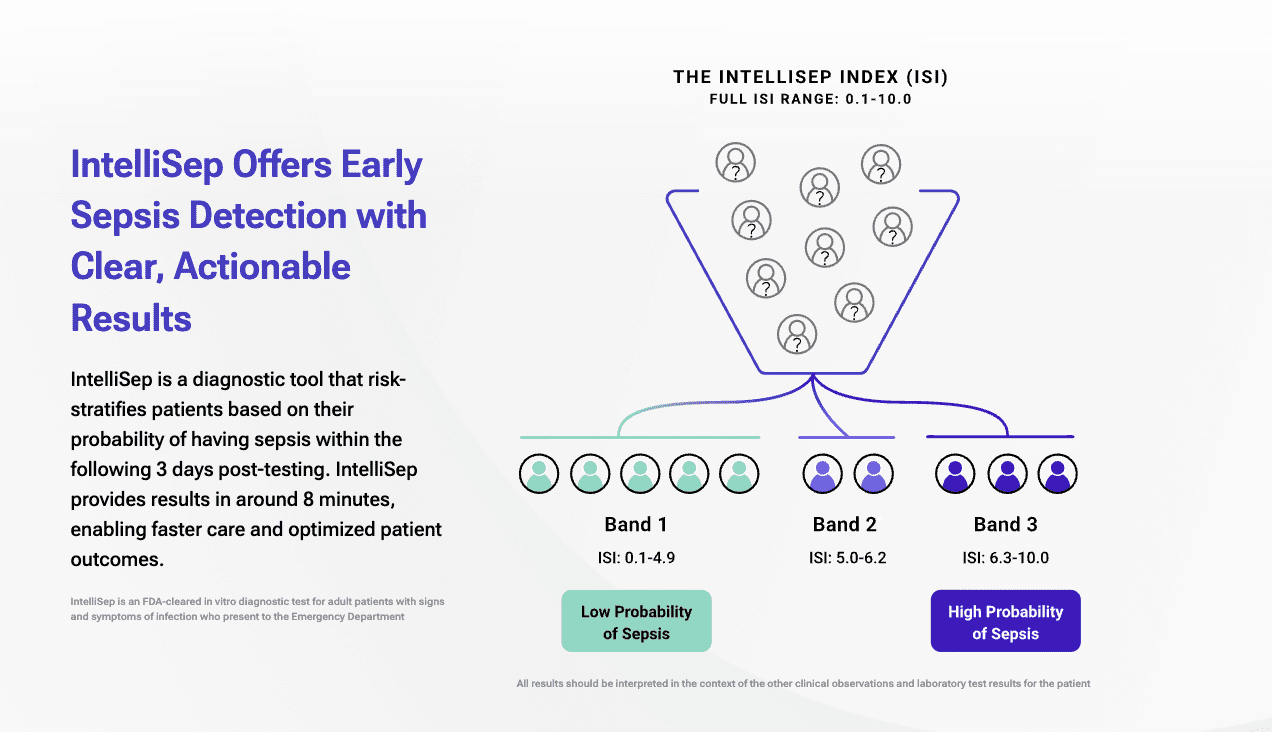

Cytovale Secures $100M to Expand Commercialization of FDA-Cleared Sepsis Test

– Cytovale, a medical diagnostics company revolutionizing early disease detection secures $100M in Series D funding round led by Sands Capital with participation from new investor Canada Pension Plan Investment Board…